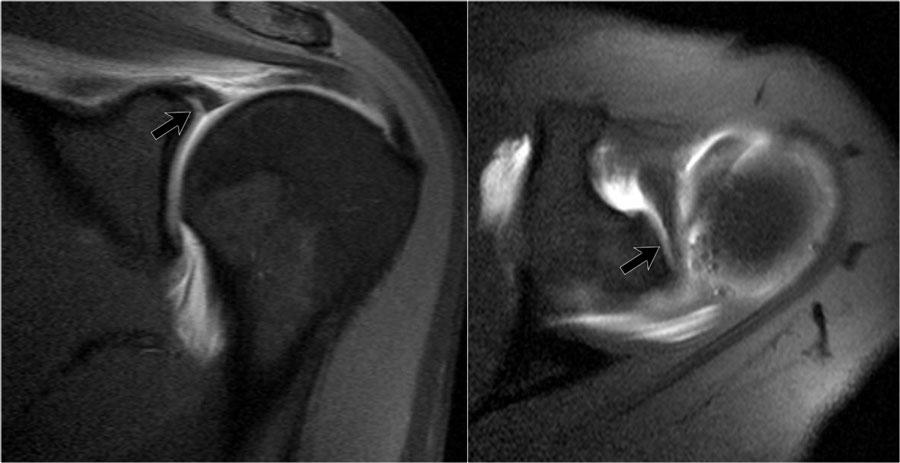

Tư thế ABER

Rách sụn viền

Tư thế dạng tay-xoay ngoài (ABER) rất hiệu quả trong việc đánh giá sụn viền trước-dưới ở vị trí 3-6 giờ,

nơi hầu hết các trường hợp rách sụn viền xảy ra.

Ở tư thế ABER, dây chằng ổ chảo-cánh tay dưới bị căng ra, tạo lực kéo lên sụn viền trước-dưới, cho phép thuốc tương phản từ nội khớp thấm vào giữa vị trí rách sụn viền và ổ chảo.

Rách chóp xoay

Tư thế ABER cũng rất hữu ích cho cả rách chóp xoay một phần lẫn toàn bộ chiều dày.

Động tác dạng tay và xoay ngoài giải phóng sức căng trên chóp xoay so với mặt cắt vành tiêu chuẩn khi cánh tay ở tư thế khép.

Kết quả là, các vết rách một phần chiều dày nhỏ ở mặt khớp sẽ không bị áp sát vào các thớ sợi còn nguyên vẹn liền kề của chóp xoay

cũng như không bị che khuất bởi chỏm xương cánh tay, và thuốc tương phản từ nội khớp có thể giúp hiển thị rõ hơn vị trí rách (3).

Hình ảnh ở tư thế ABER được thu nhận theo mặt phẳng ngang, lệch 45 độ so với mặt phẳng vành (hình minh họa).

Ở tư thế đó, vùng 3-6 giờ được chụp theo mặt phẳng vuông góc.

Lưu ý mũi tên đỏ chỉ một tổn thương Perthes nhỏ, không thấy được trên các mặt cắt ngang tiêu chuẩn.